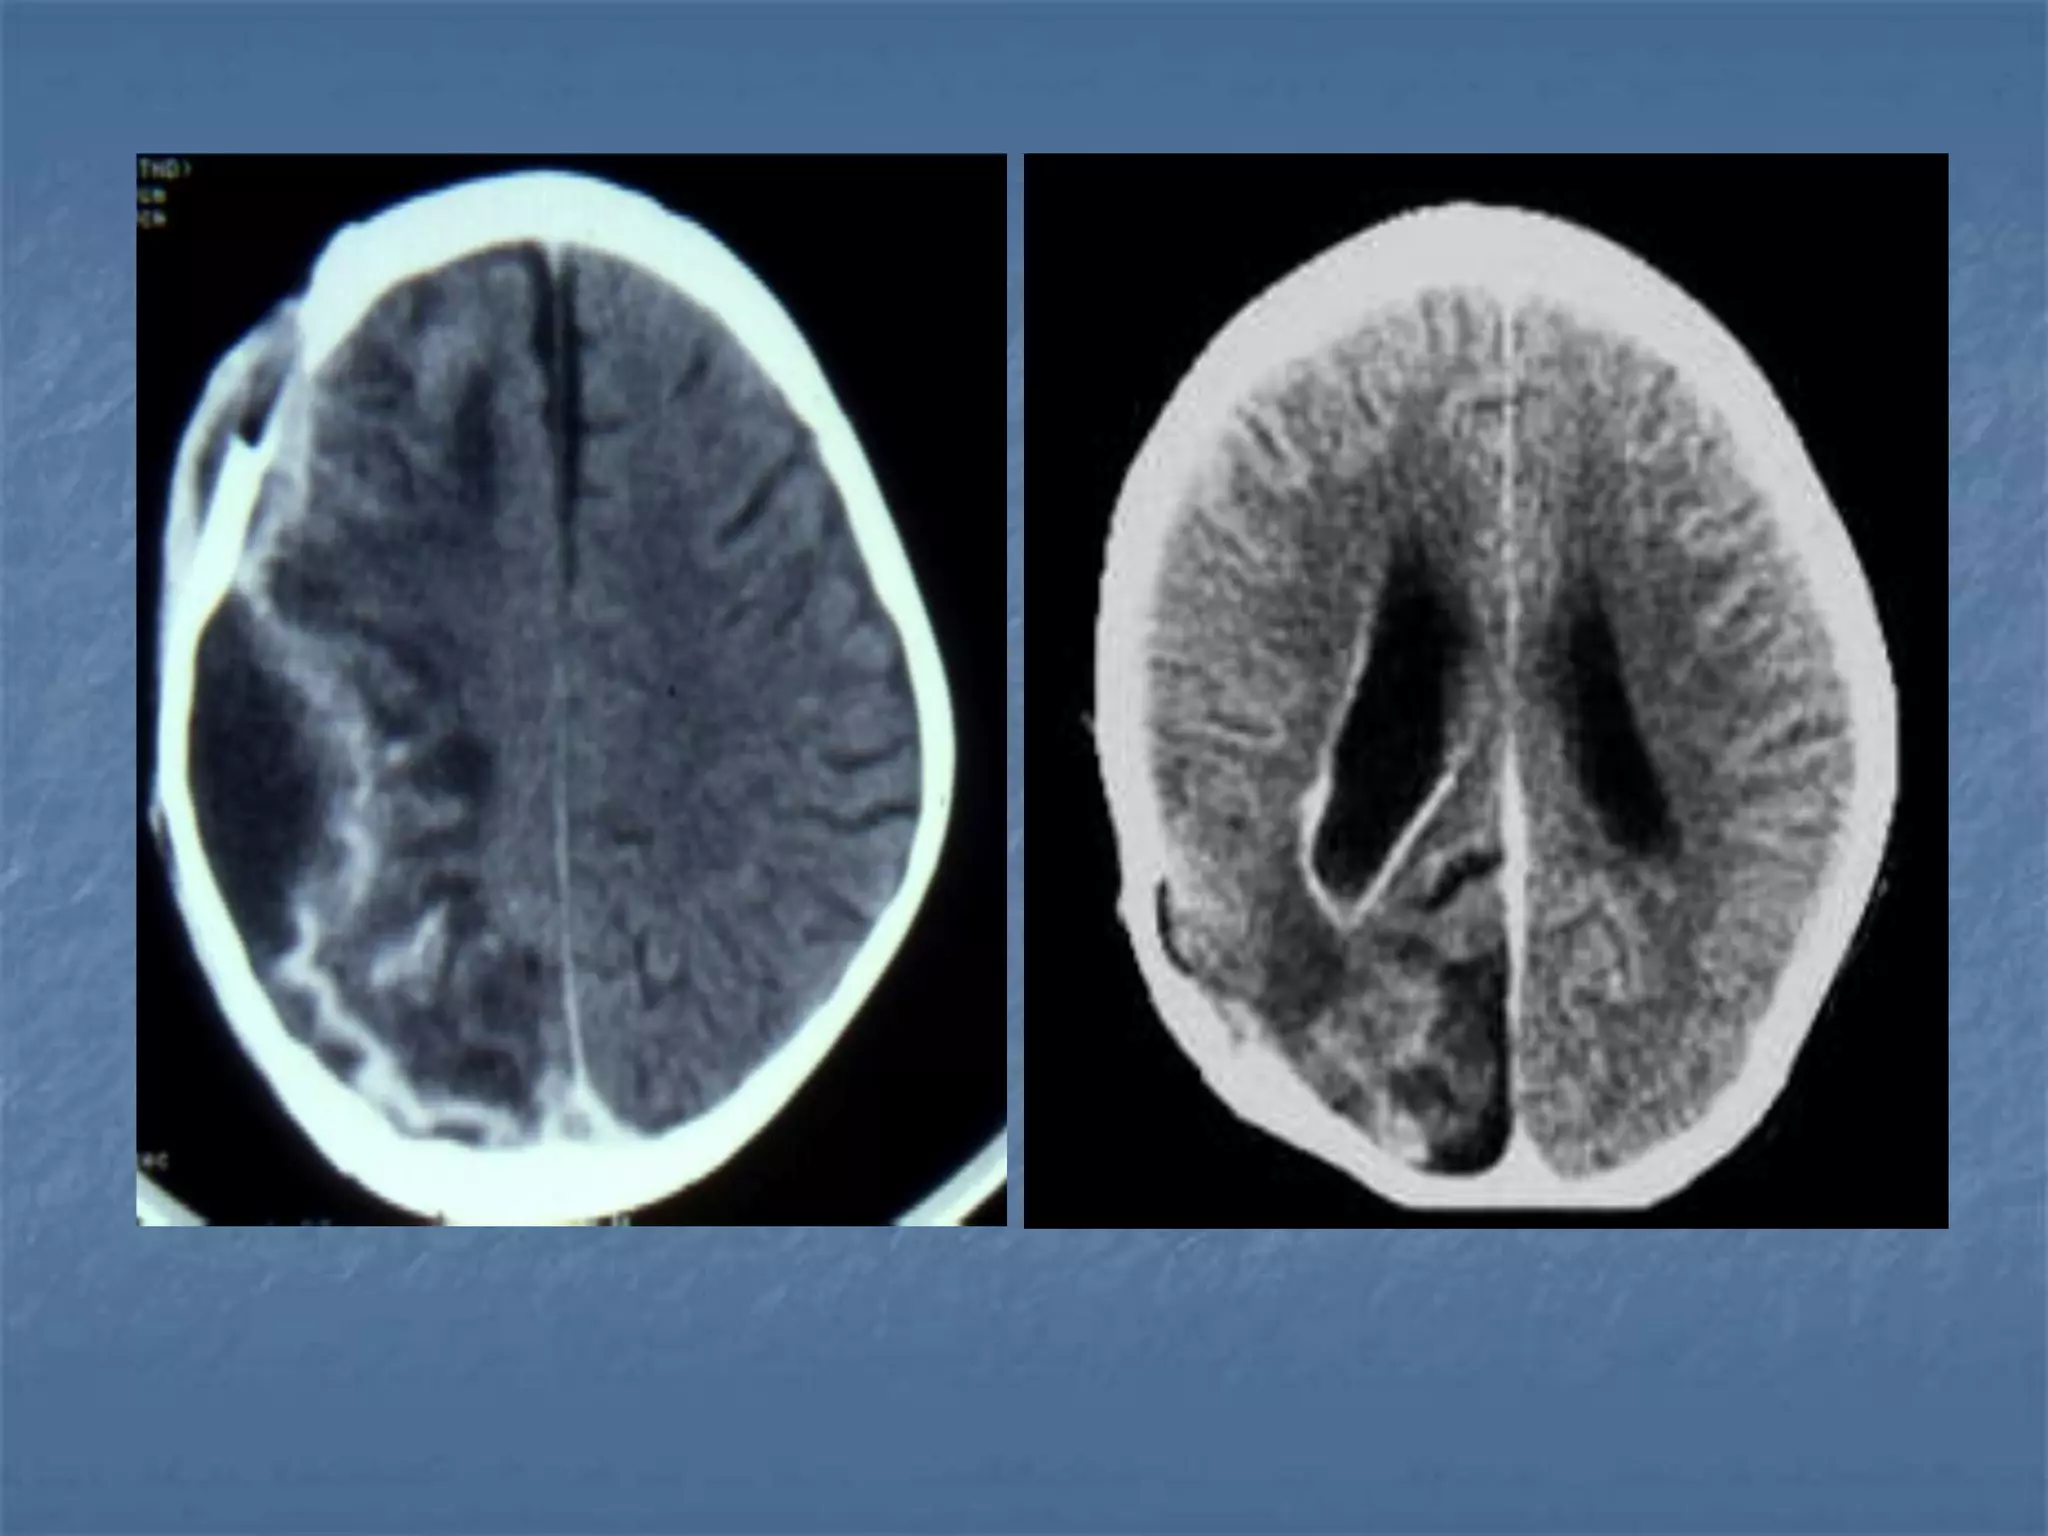

Hypertensive Hemorrhage

 Hypertensive hemorrhage accounts for

approximately 70-90% of non-traumatic primary

intracerebral hemorrhages. It is commonly due to

vasculopathy involving deep penetrating arteries

of the brain. Hypertensive hemorrhage has a

predilection for deep structures including the

thalamus, pons, cerebellum, and basal ganglia,

particularly the putamen and external capsule.

Thus, it often appears as a high-density

hemorrhage in the region of the basal ganglia.

Blood may extend into the ventricular system.

Intraventricular extension of the hematoma is

associated with a poor prognosis.

Haemorrhagic StrokeEtiology

 Hypertension

 Vascular malformation

 Aneurysm

 Trauma

 Amyloid angiopathy

 Tumor

 Coagulopathy

 Hemorrhages can occur in the intraparenchymal,

subarachnoid, intraventricular, subdural and

extradural spaces.

 Location of hypertensive hemorrhage:

Putamen, external capsule, thalamus, pons,

cerebellum, subcortical white matter